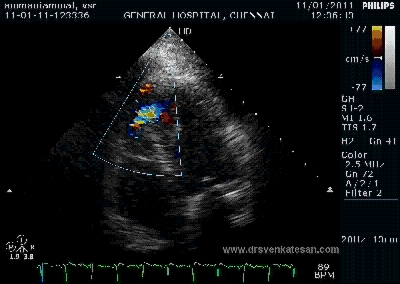

Here is 55 year old women came with extensive anterior MI with lower septal rupture.(She belonged to type 3 of the above scheme)

Note the septal rupture is visible even in 2D Echo

Color flow showing significant shunting from LV to RV.This shunt depends upon the LV contractile function, LVEDP and ofcourse the RV pressure

If there is severe RV dysfunction or bi ventricular dysfunction flow across the defect is inconspicuous.Brisk left to right shunting may be an indirect marker for good LV systolic function and absence of significant pulmonary hypertension.Both imply a better outcome.